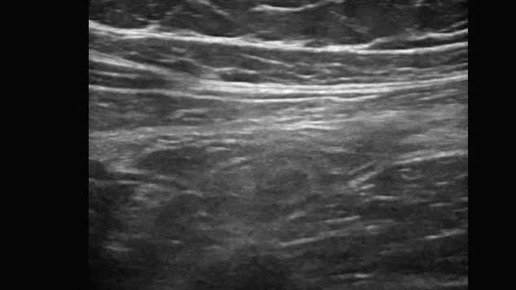

Ультразвуковые находки от врача УЗД Зорина Я.П.